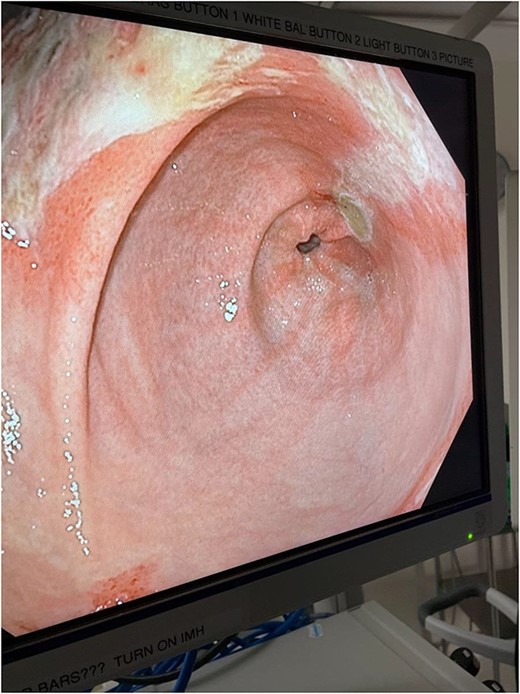

The decision was made to take the patient to the operating room. He underwent diagnostic laparoscopy, which showed a normal gastric antrum; however, on further inspection, a hemorrhagic and inflamed area of stomach was seen proximally at the fundus on the underside of the diaphragm. Next, esophagogastroduodenoscopy was performed, which demonstrated a large black necrotic area in the fundus (Fig. 3), as well as inflammation throughout the rest of the gastric body (Figs 4 and 5). At this point, malignancy could not be ruled out, so the operation was converted to open with a subxiphoid to supraumbilical midline incision. Once in the abdomen and able to further inspect the stomach, the frankly necrotic portion of fundus was noted to be adhered to the underside of the diaphragm and a contained purulent fluid collection was encountered in this area and drained. A partial gastrectomy was then undertaken in similar fashion to a sleeve gastrectomy. The lesser sac was entered and the stomach mobilized along the greater curvature with an energy device up through the short gastrics. A stapler was used to resect the entire necrotic portion of stomach from the midbody to the angle of His. Frozen sections were sent which were negative for malignancy. The remaining stomach was inspected for signs of malignancy, but none were found. For these reasons, no further resection was done. The entire staple line was imbricated due to concern for an ischemic etiology for the patient’s disease process, and two drains were left—one anterior and one posterior to the staple line. Final pathology showed prominent gangrenous necrosis, ulcer and acute necro-inflammatory exudate. Most of the specimen had no viable gastric mucosa, and no malignancy was found.

Intraoperative endoscopic image: inflammatory changes of gastric mucosa in midbody of stomach.